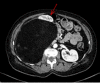

Figure 1. Case 1. Contrast-enhanced abdominal CT scan

This shows a retroperitoneal adipocytic mass displacing the right colon and kidney to the left (red arrow).